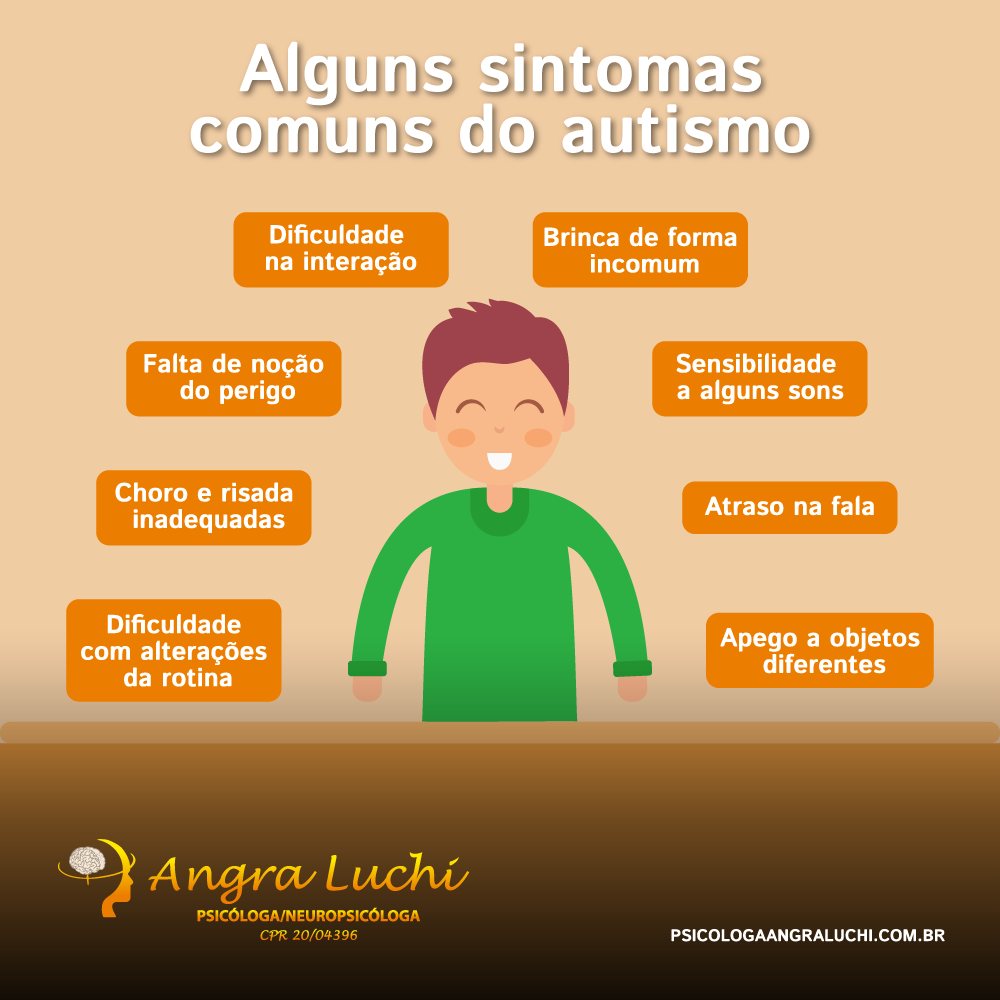

Alguns sintomas do Autismo - Psicologa Angra Luchi

Sintomas de autismo04 abril 2025